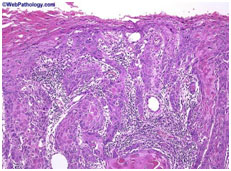

- Основная гистологическая форма рака полового члена – плоскоклеточный рак, который составляется 95% всех опухолей полового члена и проявляется кератинизацией, эпителиальными «жемчужными» образованиями и другими видами митотической активности. Нормальное строение тканей полового члена нарушается, происходит инвазия и пенетрация опухоли через базальную мембрану окружающие структуры. Высокодифференцированнный плоскоклеточный рак полового члена характеризуется утолщением эпидермиса, гиперкератозом, папилломатозом и растущими вглубь пальцевидными выростами атипичных шиповатых клеток с наличием в толще комплексов концентрических образований, состоящих из уплощенных клеток с ороговением в центре («роговых жемчужин»); эпителиальные клетки имеют интактные десмосомы и легкую атипию, увеличенные плеоморфные ядра, встречаются фигуры митозов; в толще дермы обнаруживается плотный лимфоцитарный или смешанный воспалительный инфильтрат.